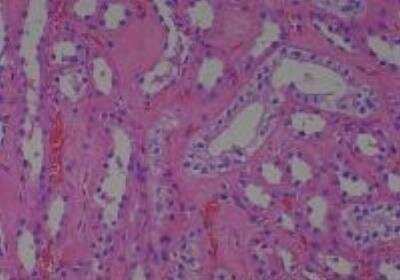

Hematoxylin & Eosin Stain: Human Common Tissue MicroArray (Normal Adjacent) [NBP2-30215] - 102. Stomach